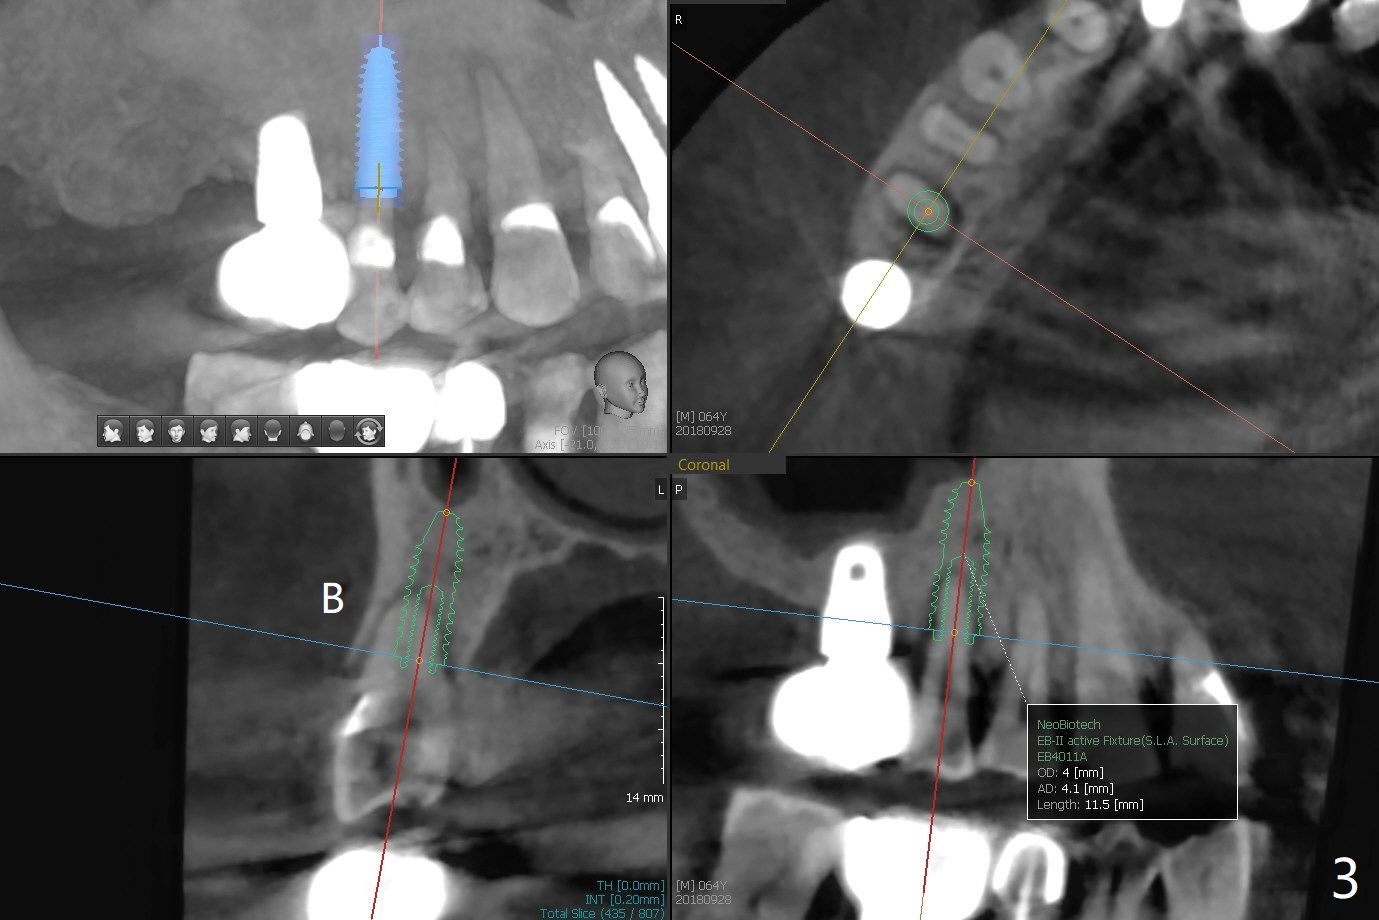

67岁男三年前CT显示4号牙牙周膜增宽(图一),最近咬到米粒中沙子突然松动(图二),要求退休前拔除种植(图三)。